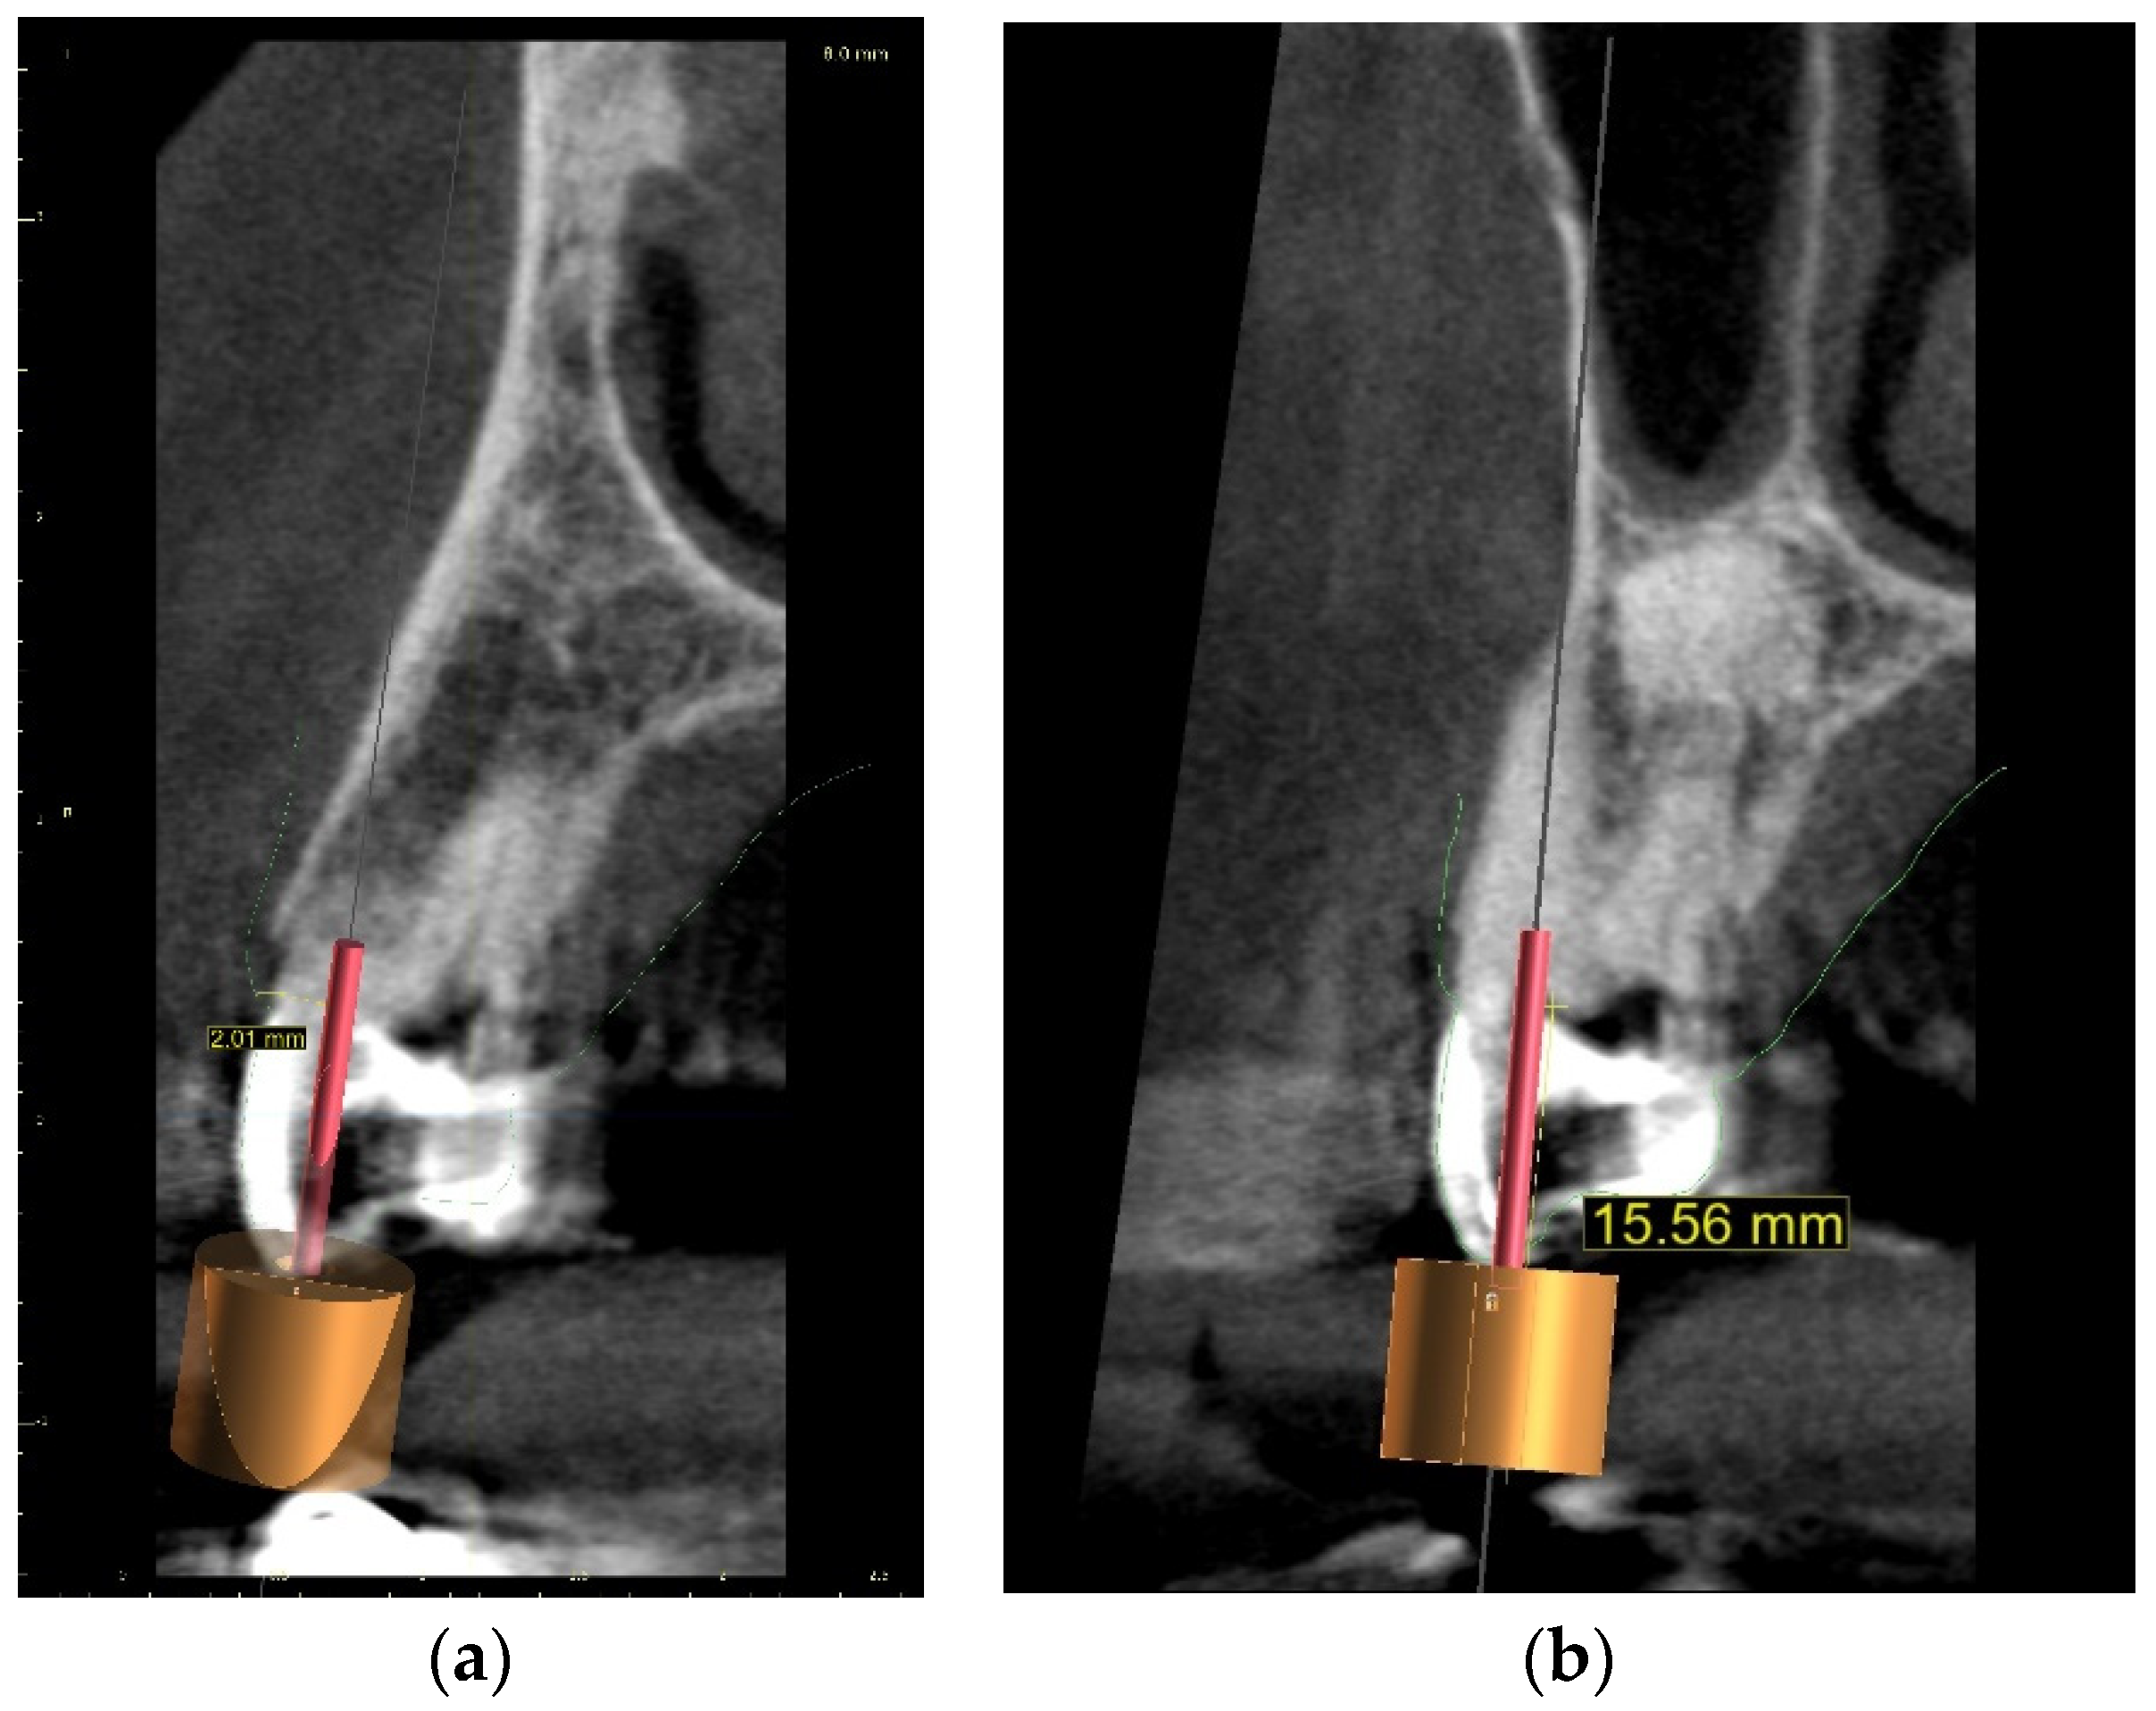

The guided endodontics demanded more complex planning in this case due to artefacts caused by metal restoration in a neighbouring tooth (the second premolar, tooth 25) and the completely nonvisible root canal. According to Buchgreitz et al., when CBCT does not allow clinicians to visualize the canal, the target point in single-rooted teeth can be established through the centre of the root, as seen in the axial view [25]. Despite the fact that tooth 24 is not a single-rooted tooth, in this case, the virtual drill orientation was defined through the centre of the buccal root. A margin of 2 mm to ensure sufficient root dentine thickness was preserved, as there was no visible part of the root canal. The top of the sleeve was 15.5 mm from the bottom of the tooth chamber. The guide sleeve was 6.5 mm long and 1 mm in diameter (Figure 20). The teeth-supported guide was designed with an embossed canal marking (Figure 21).

Figure 20. CBCT image presenting (a) virtual implant positioned through the centre of the buccal root, preserving a safe amount of the tooth’s hard tissues; (b) guide tube designed to reach the bottom of the chamber after 15.5 mm. In the lateral dentition area, short guide tubes may ensure more space for the drill.